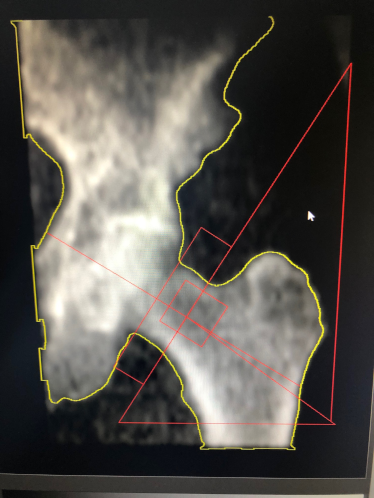

Bei der Knochendichtemessung werden die Dichte des Oberschenkelhalses und der Lendenwirbelsäule mit einer speziellen strahlungsarmen Röntgentechnik erfasst, die BMD (Bone Mineral Density).

Die wichtigste und am weitesten verbreitete Methode zur Messung der Knochendichte ist die DEXA Methode. (Dual Energy X-Ray Absorptiometry).

• Sie misst die für die Osteoporose empfindlichsten und frakturgefährdetsten Skelettareale (Lendenwirbelsäule und Hüfte).

Bei dieser DXA-Messung werden die Ergebnisse mit den Messwerten von gesunden jungen Erwachsenen in Relation gesetzt und der sogenannte T-Wert ermittelt.

T-Wert -1 oder höher = normale Knochendichte

T-Wert -1 bis -2,4 = Osteopenie (Knochenarmut)T-Wert -2,5 oder niedriger = Osteoporose